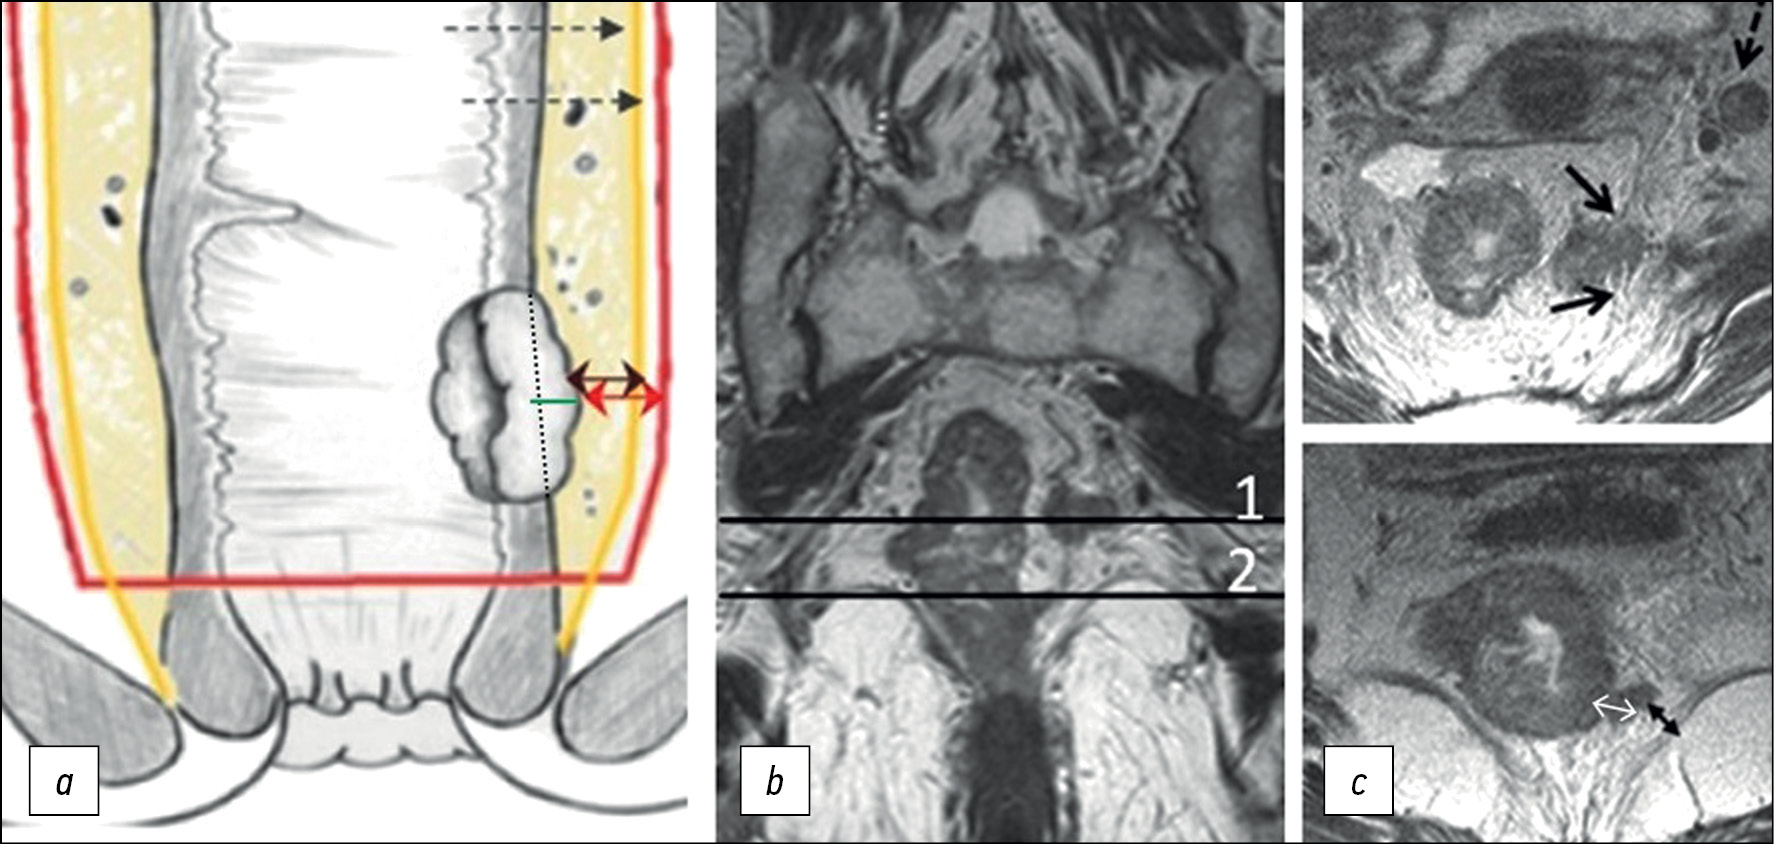

The depth of extramural invasion is the maximum distance from the outer edge of the muscular layer of the wall at the base of the extramural component of the primary tumor to its outer edge, as observed on high-resolution T2-WI oriented perpendicular to the intestinal wall at the level of the tumor (Fig. 2). The depth of extramural invasion is used to determine the substage of T3 tumors.

Fig. 2. Circular border (edge) of rectal resection during total mesorectumectomy. (a) Diagram showing extramural growth of the tumor (green line); mesorectal fascia (yellow line); circular border (edge) of resection (red line); distance from the tumor to the mesorectal fascia (double black arrow); distance from the tumor to the circular border (edge) of resection (double red arrow). (b) T2-weighted images in the coronal plane of the tumor of the lower ampullary part of the rectum with extramural vascular invasion and deposit at the level of axial T2-weighted images. (c) Upper axial section corresponds to the level of the deposit involving the mesorectal fascia (black arrows), extramesorectal lymph node (dotted arrow). The lower axial section corresponds to the level of extramural vascular invasion. The depth of extramural invasion (a double white arrow). The distance from the tumor to the elevator muscle of anus (a double black arrow).

Circumferential resection margin (CRM) is a surgery and pathology term defined as the surface of surgical excision of the non-peritoneal part of the rectum, which should pass along the mesorectal fascia when performing a total mesorectumectomy.

The status of CRM is determined by histological examination of the surgically removed rectum specimens. It can be predicted based on MRI by the shortest distance between the extramural component of the tumor/deposit/affected lymph node and the mesorectal fascia. Involvement of the CRM is indicated as CRM(+) if this distance is ≤1 mm. For low-lying rectal cancer, the shortest distance is determined to the elevator muscle of anus. The distance from enlarged lymph nodes without signs of extracapsular spread (with smooth contours) is not considered and should be regarded as CRM(−) [13].